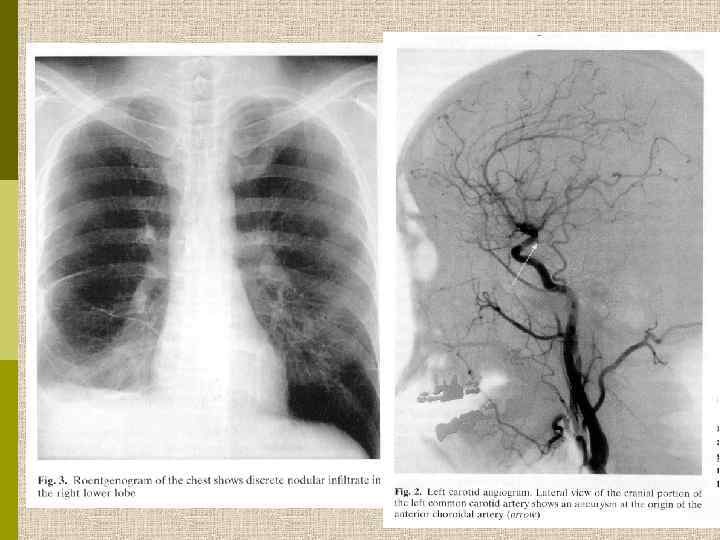

Окклюзия левой подключичной артерии вскоре после её отхождения от аорты. Результат – отсутствие пульса на левой руке. В процесс чаще вовлекается дуга аорты и отходящие от нее коронарные артерии, подключичные и почечные артерии. В артериях – гранулематозное воспаление, аневризмы и расслаивание стенки. В поздних стадиях – фиброз. Иногда поражаются легочные артерии.